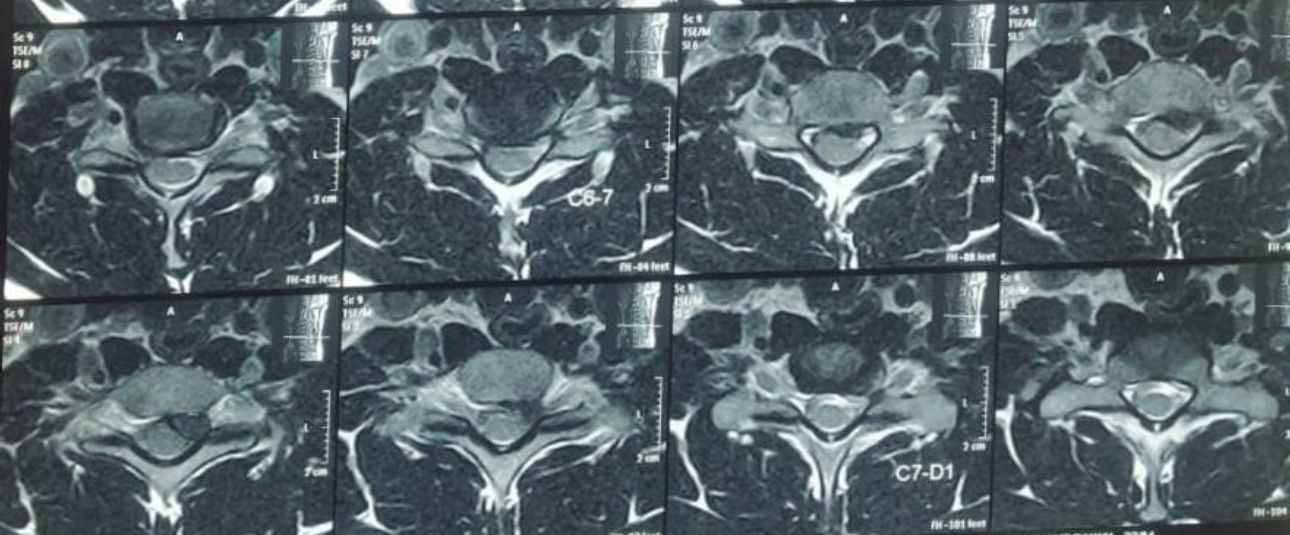

- Intramedullary Tumors begin in the cells within the spinal cord itself, such as gliomas, astrocytoma or ependymomas.

- Extramedullary Tumors grow in either the membrane surrounding the spinal cord or the nerve roots that reach out from the spinal cord. Although they don’t begin within the spinal cord itself, these types of tumors may affect spinal cord function by causing spinal cord compression and other problems. Examples of extramedullary tumors that can affect the spinal cord include meningiomas, neurofibromas, schwannomas and nerve sheath tumors.